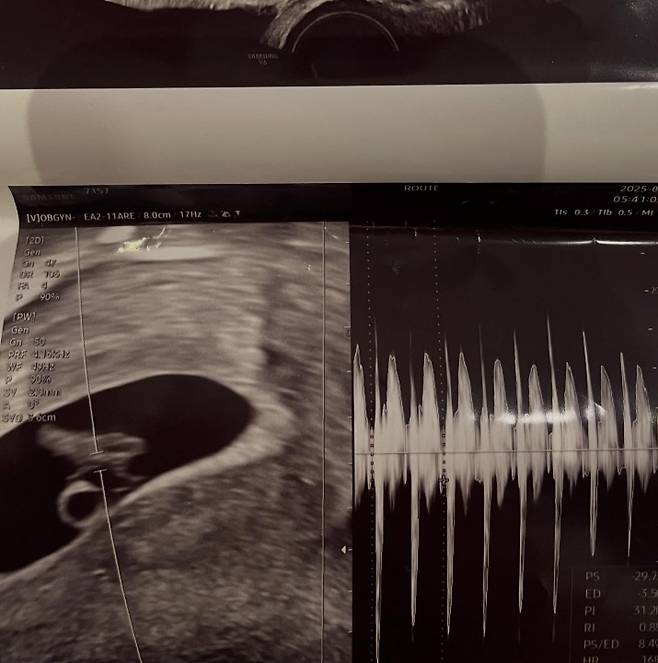

그러면서 서민재는 A씨의 인스타그램 계정과 그가 다니는 듯한 회사와 학교 등을 태그하며 연락을 압박하는 것으로 보인다. 앞서 서민재는 초음파 사진과 함께 임신 사실을 공개했고, 남자친구의 실명을 공개하며 "20학번이고, 97년생"이라고 밝힌 바 있다.